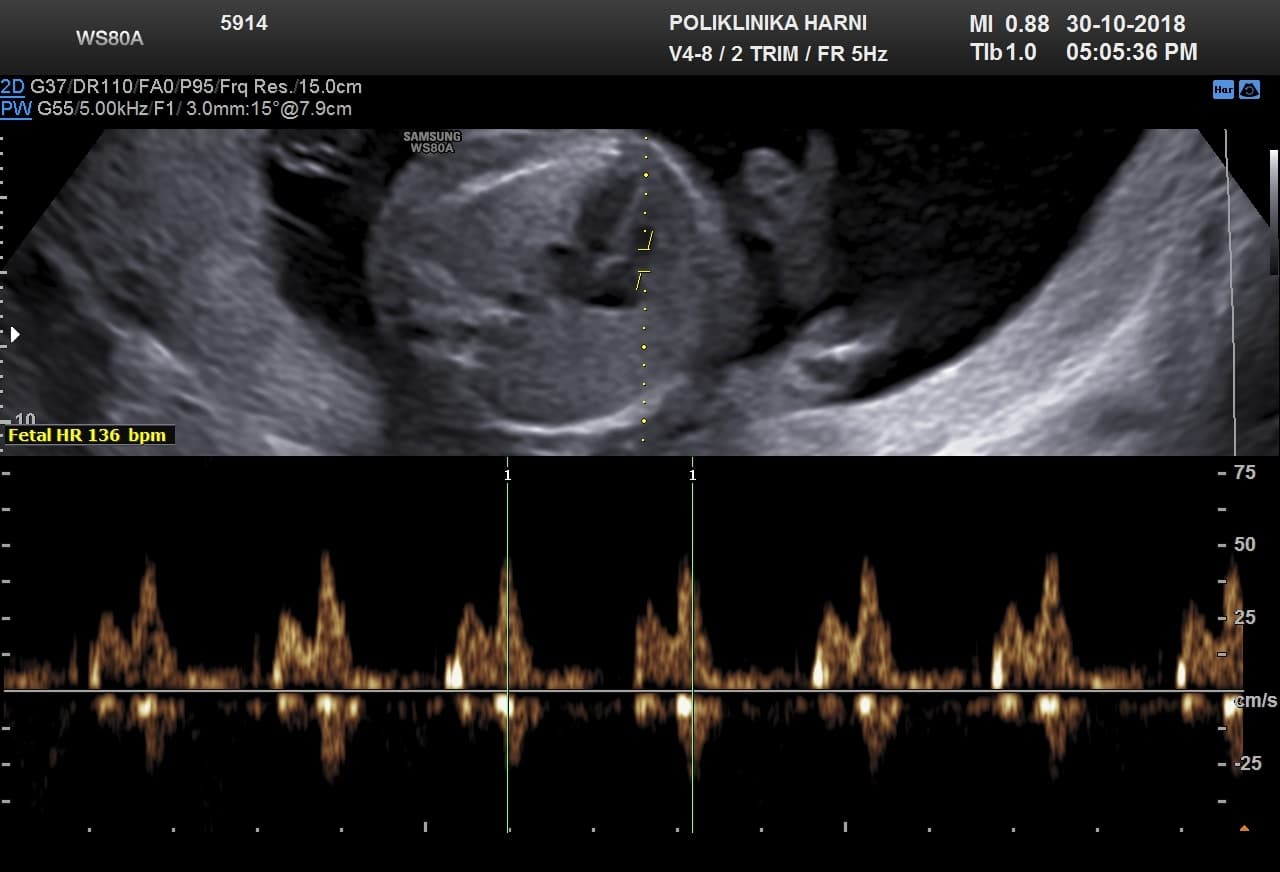

Oko 20. tjedna trudnoće obično se obavlja detaljan ultrazvučni pregled drugog tromjesečja, poznat kao morfološki ultrazvuk ili anomaly scan. Tijekom tog pregleda procjenjuju se razvoj i anatomija fetusa, razvoj mozga, srca i drugih organa, količina plodove vode te položaj i izgled posteljice.

Ovaj pregled omogućuje liječniku da procijeni razvija li se beba uredno te pruža važan uvid u tijek trudnoće, kao i da preporuči dodatne pretrage kao što su fetalna neurosonografija ili fetalna ehokardiografija.